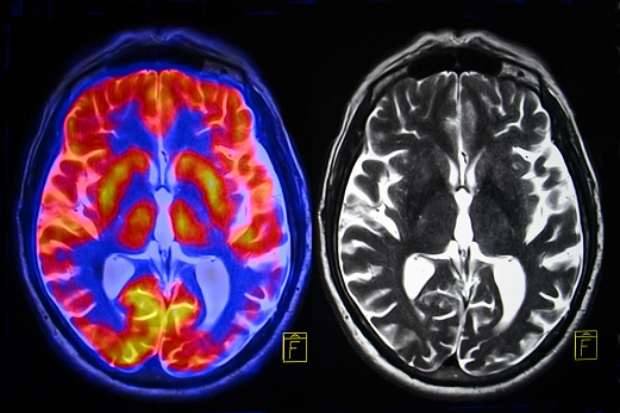

Increased need for sleep a warning sign for dementia?

New research has found an association between seniors who suddenly begin sleeping longer hours and an increased risk of dementia. Older adults who began sleeping more than nine hours a night saw their risk of developing dementia later in life more than double, while those who found they suddenly needed more sleep and did not ...click here to read more